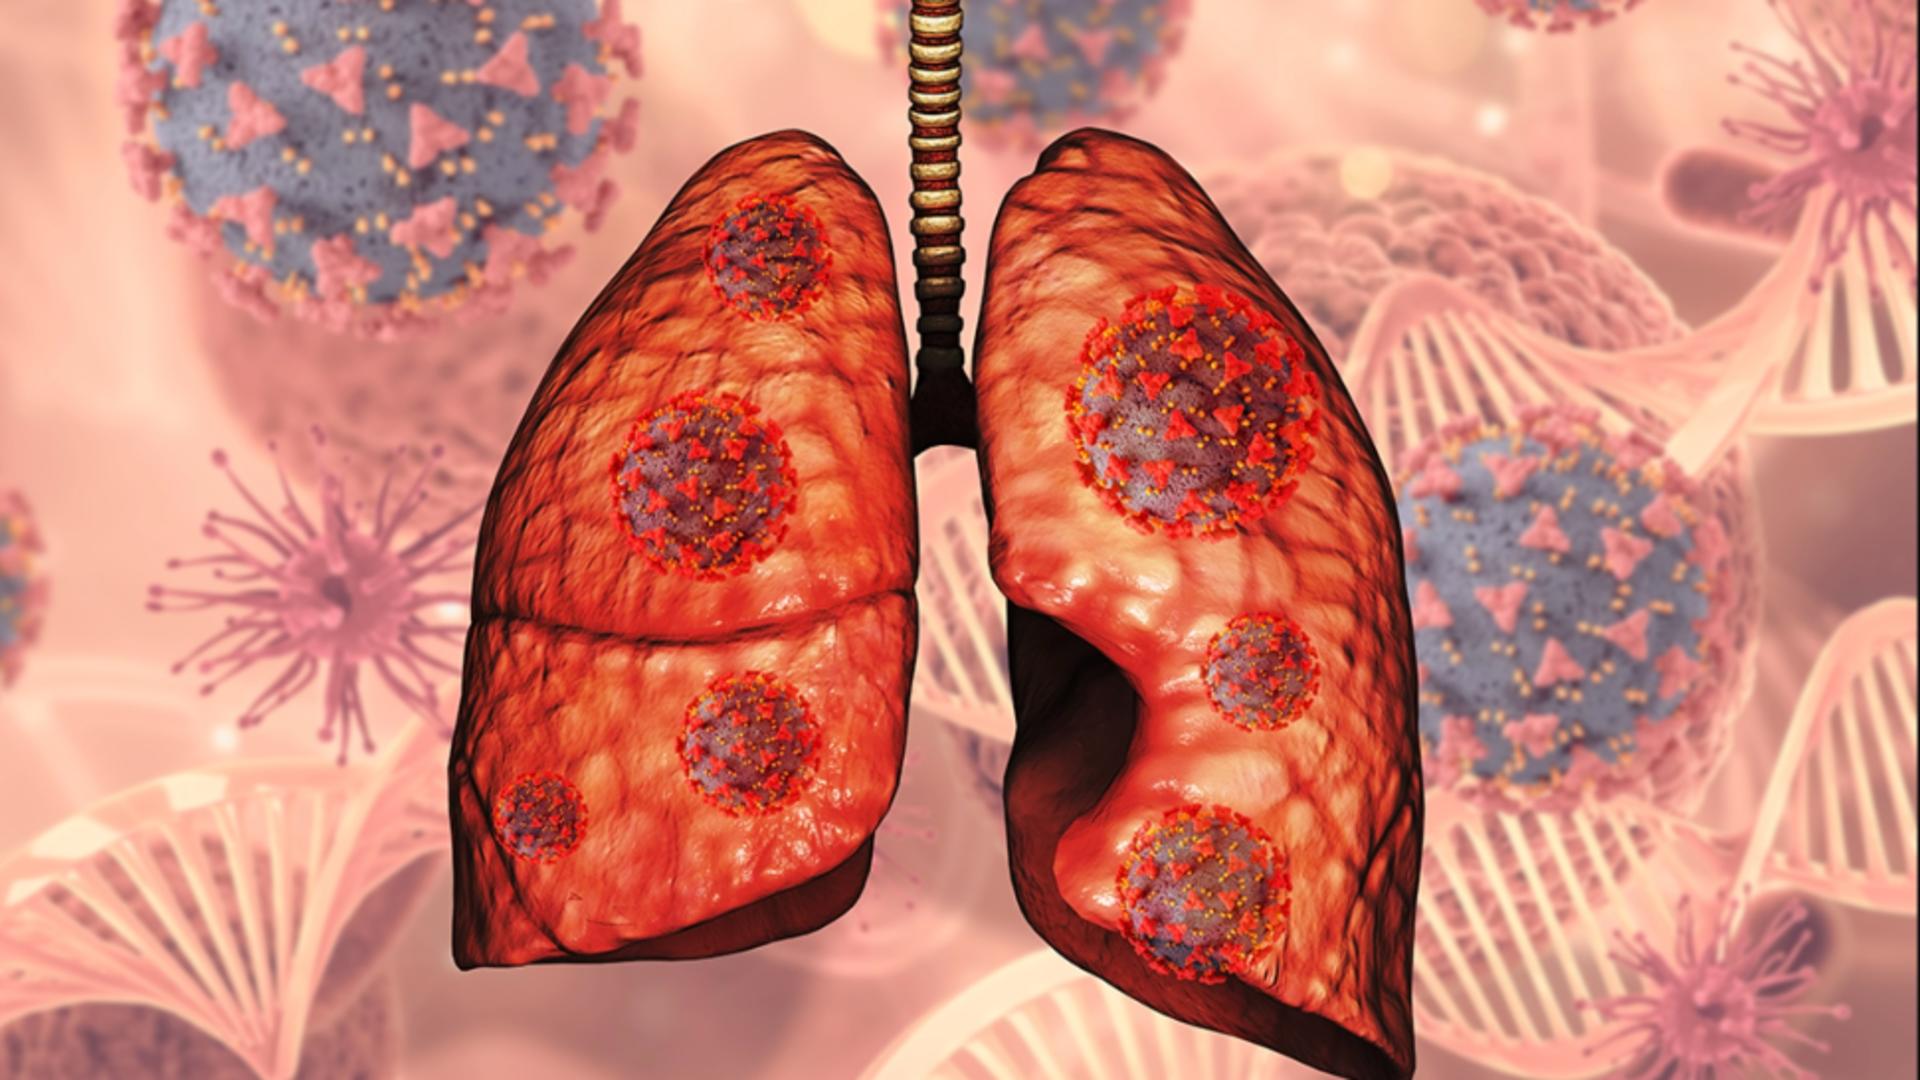

Fibroza chistică este o afecțiune care nu se vindecă, agravându-se în timp, ceea ce face ca speranța de viață a bolnavilor să fie mai redusă comparativ cu cea a oamenilor sănătoși. Boala afectează în special respirația și nutriția, pacienții confruntându-se cu infecții frecvente. Gestionarea bolii se face cu ajutorul medicației, curățarea căilor respiratorii și a dietei, necesitând îngrijire zilnică.